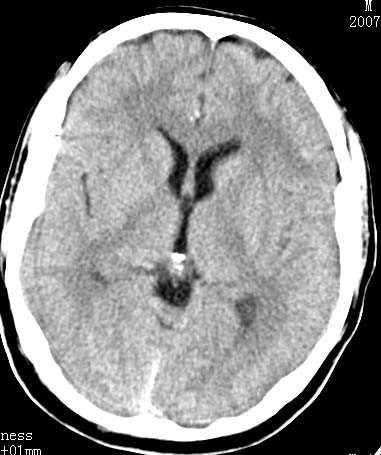

以下是引用卜一在2007-8-29 6:48:00的发言:[br]左侧额叶不均匀密度影,占位效应明显,界限不清。支持:占位性病变,建议增强!

以下是引用jiangjing在2007-8-29 14:33:00的发言:[br]左侧额叶不均匀密度影[低密度为主,边缘见等密度环环绕]占位效应明显,界限不清。支持:占位性病变,建议增强! [br][br]